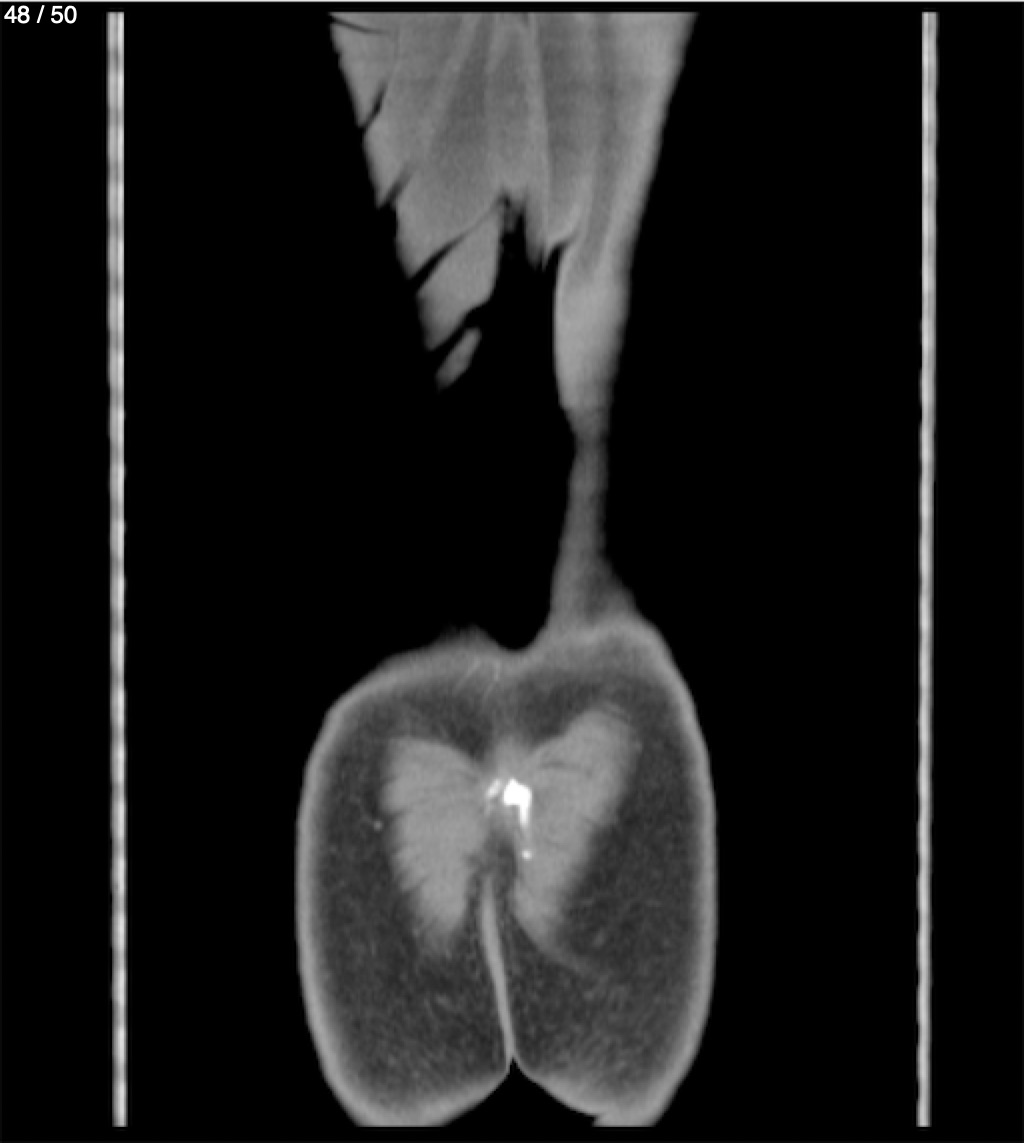

Alonso Victorio Ruiz 62A - T.C Abdomen Syc